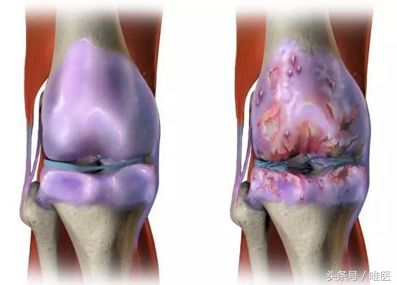

骨关节炎本身就是一种以软骨退变为核心的关节病变,并逐渐累及骨质并包括滑囊、关节囊及关节其它结构的全方位、多层次、不同程度的慢性炎症。由于膝关节是人体最大的负重关节,所承受的压力负荷最大,所以是最常见的发病部位。

简单的说,就是膝盖表面的软骨像墙皮一样一块块的磨损剥脱,并且不能重新修复。随着病变程度的加重,软骨损伤的范围也会逐渐增加,症状往往也就随之加重。早期的膝骨关节炎会在爬山或较大量的活动后出现;逐渐的,在日常的上下楼,蹲下站起时患者会感觉膝关节酸痛;再发展下去,会在久坐站起时行走困难,并逐渐出现膝关节无法完全伸直,出现O型腿,也就是膝关节内翻畸形,关节持续肿痛。